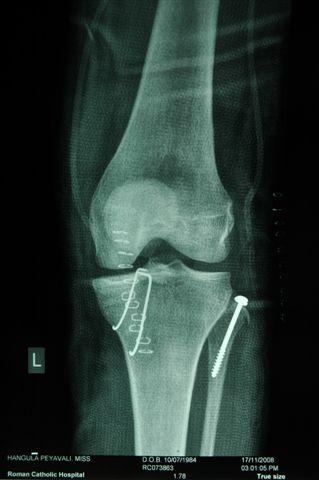

Как вариант фиксации межмыщелкового возвышения предлагаю фиксацию двумя спицами - технически гораздо проще , чем проволочной петлей и вполне стабильно.

В приложении Ргграммы- спицы проводятся ретроградно через фрагмент возвышения, загибаются, подтягиваются  и загибаются со стороны внутреннего мыщелка.